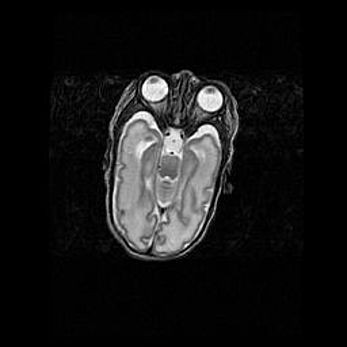

Неполная лизэнцефалия (пахигирия). Открытая гидроцефалия.

Возраст: 17 дней

Вес: 3110 г

Пол: мужской

Окружность головы: 33,5 см

Срок гестации: 35-36 недель

Лизэнцефалия—недоразвитие корковой пластинки и мозговых извилин в результате нарушения миграции нейронов коры. Поверхность мозговых полушарий гладкая. Микроскопически выявляется отсутствие нормальных слоев коры и скопление групп нейронов в подкорковом белом веществе.

Пахигирия—уменьшение числа вторичных извилин. В пораженном полушарии нервные клетки образуют толстый недифференцированный слой с неправильно расположенными нервными волокнами и группами гетеротопных клеток. Нервные клетки незрелые. Белое вещество истончено. При этом нередко аномально развит корково-спинномозговой путь.